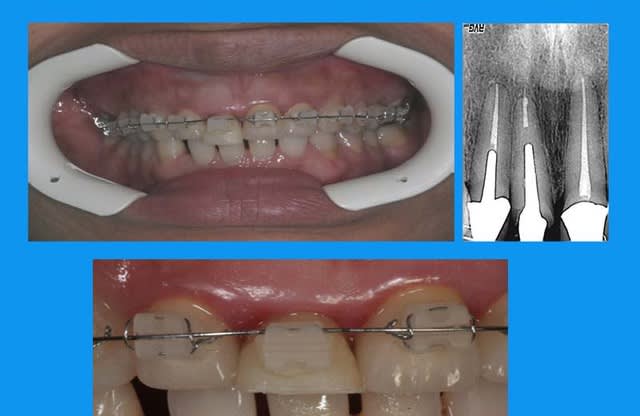

l'odf a utilisé un arc 0.014 thermique ,force constante faible

la dent provisoire a été meulée au fur et à mesure de la traction = 3mm

Tu n'as donc pas nivellé la ligne des collets ?

n'ayant pas ton coup de bistouri,j'ai reculé,mis en attente et prié...

la fracture était basse en vestibulaire,la gencive assez fine et je n'ai pas "senti" le remodelage gingival sur la provisoire(qu'en termes corrects ma peur de rater peut être exprimée:)

d'où l'empreinte avec bague de Cu pr aller chercher les limites

entre temps il y a de l'odf pr réaligner les incisives du bas(diastèmes se modifient d'après la patiente), à la demande de la patiente et parceque la fracture de 11 au bout de tant d'années me questionne...

autre question:"les incisives du bas"

la patiente a entamé son traitement odf pr une demande esthetique(marre des diastème)

pr des raisons fonctionnelles aussi,cela ns paraissait une bonne idée

elle a une microdontie relative de ces insicives qui st maintenant redressées, alignées avec des diastèmes equidistants

et maintenant....

que feriez vous?